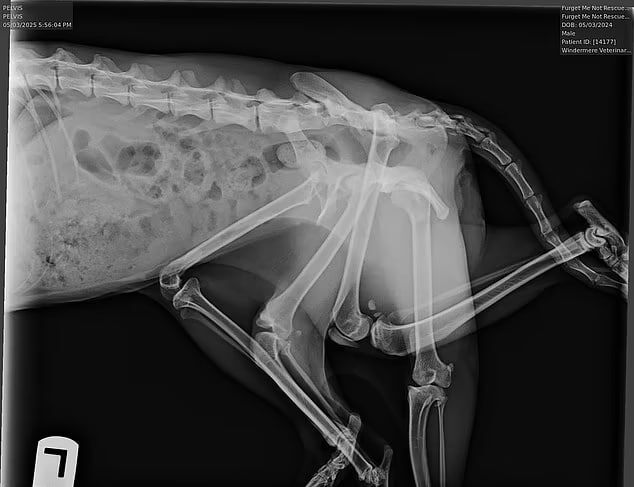

В Англии родился шестилапый кот. Один эмбрион сожрал другого — остались лапы напоминать. Дополнительные конечности торчат, но коту плевать: бегает, жрёт, радуется жизни. Врачи утверждают — жить будет, хвост не отвалится. Хозяин резать не спешит: мешать начнут — тогда поговорим.

В Англии родился шестилапый кот. Один эмбрион сожрал другого — остались лапы напоминать.

Дополнительные конечности торчат, но коту плевать: бегает, жрёт, радуется жизни.

Врачи утверждают — жить будет, хвост не отвалится.

Хозяин резать не спешит: мешать начнут — тогда поговорим.